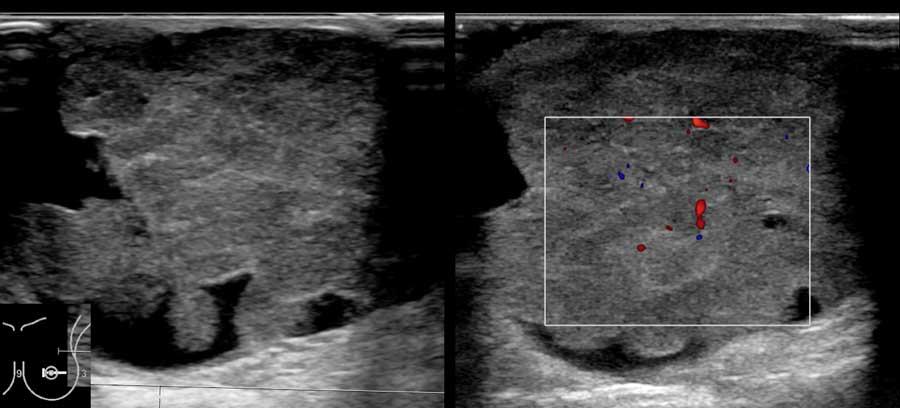

Các hình ảnh này thuộc về một phụ nữ 50 tuổi đến khám vì sờ thấy các khối ở vùng nách, tương ứng với các hạch bạch huyết to, hình tròn, giảm âm.

Tiếp theo đó, siêu âm tuyến vú được thực hiện và phát hiện một tổn thương ung thư nhỏ, giảm âm, bờ không đều, không sờ thấy được trên lâm sàng.